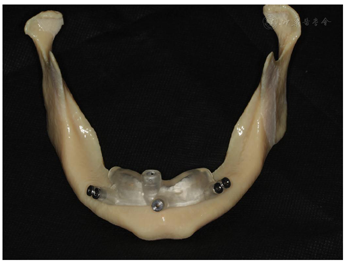

行数字化导板引导的下颌all-on-6种植手术,正畸治疗中切牙,角化龈游离移植,复合基台水平钛支架修复。

患者下颌在治疗后已恢复美观和咬合功能,达到了较为理想的修复效果。

安放骨支持式种植导板,在导板引导下用先锋钻在牙槽窝定点和定方向,种植窝直径2.4~2.8mm后停止扩孔,植入Nobel Active 3.5mm×8mm种植体,利用种植体的自攻性到达预定深度,均在骨平面以下,6颗种植体尽量保持在一个平面利于后期修复,所有种植体初期扭矩达到50N/cm,然后平整骨面,安放复合基台(图17)。